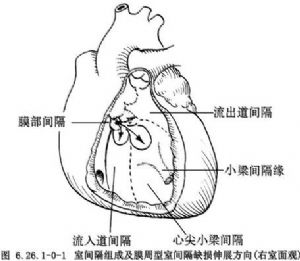

室間隔由4個部分,即膜性間隔、流入道間隔、小梁間隔、流出道間隔或漏斗部間隔組成。缺損可發生在室間隔各個部位或其交接部(圖6.26.1-0-1)。從胚胎髮育情況及分佈部位,室間隔缺損可分爲膜部間隔或膜周型間隔缺損、房室管型室間隔缺損、漏斗部或幹下型間隔缺損及肌部間隔缺損四大類型。其中膜部缺損最多見,漏斗部缺損次之,肌部缺損較少見,房室管型缺損更少見。上述各型又可分出若干亞型並有不同名稱(圖6.26.1-0-2),這種分型對手術治療有指導意義。室間隔的解剖見圖6.26.1-0-3。